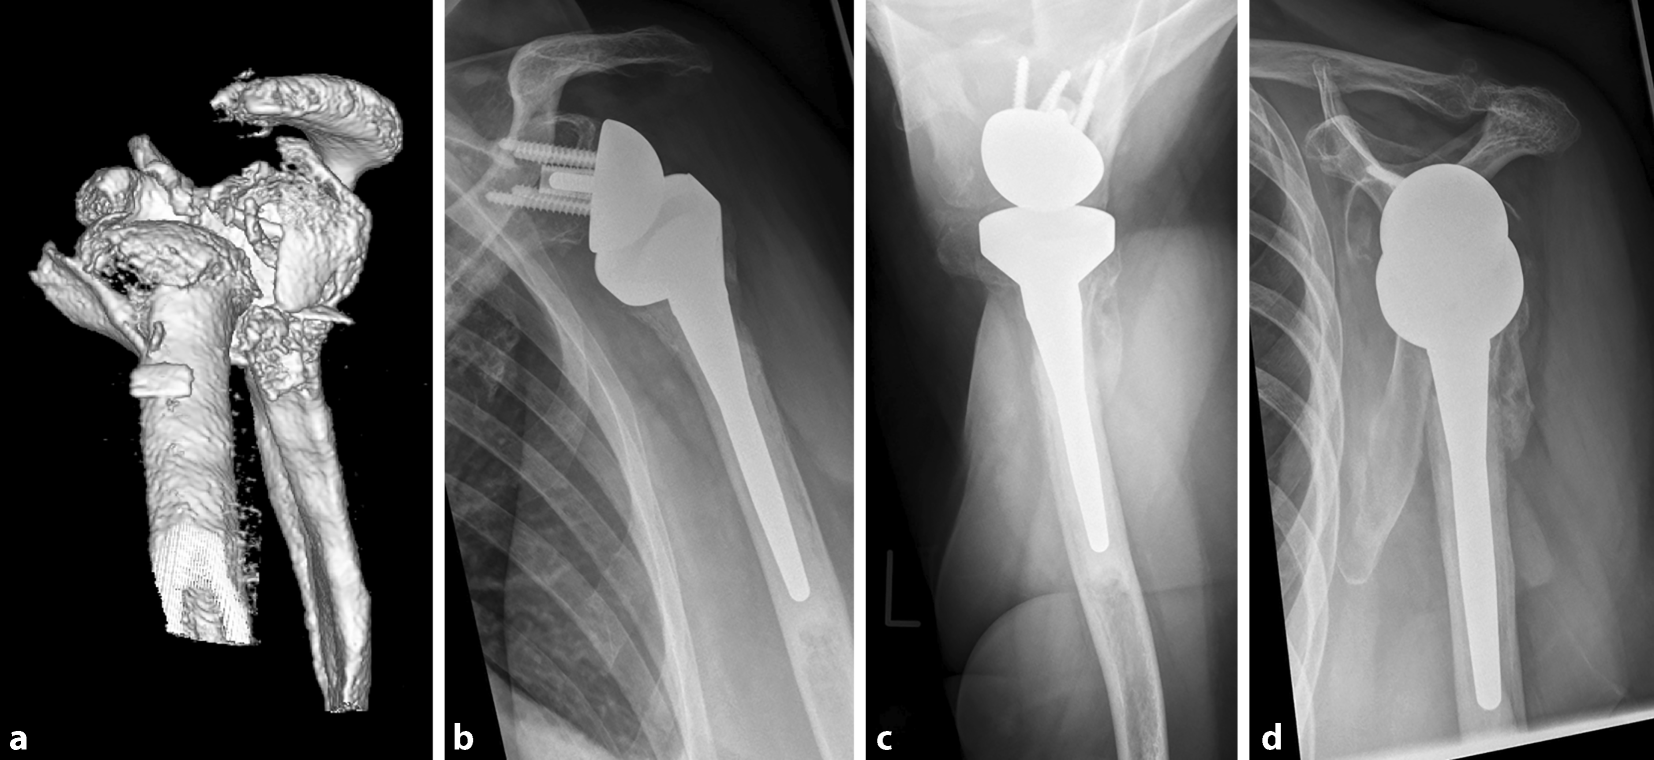

From link.springer.com

Headsplit fractures of the proximal humerus SpringerLink Split Cast Fracture 1 immediate management of these injuries includes applying a plaster cast—called a back slab—to the dorsal aspect of the forearm. The sides of the bivalve cast will be taped with cloth. you have been fitted with a cast or splint to protect your bone and reduce pain as you heal. casts are most commonly used to hold a. Split Cast Fracture.

Headsplit fractures of the proximal humerus SpringerLink Split Cast Fracture This article explains what to expect while you are wearing your cast or splint and. However, they differ in their. casts and splints hold broken bones in place while they heal. casts are most commonly used to hold a part of your body in place while you’re healing after a bone fracture (a broken bone). It is important. Split Cast Fracture.